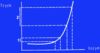

Vad visar bilden?

- Området som haft under 10 % (C på bilden) dör vanligtvis. P1/P2 har haft strax under 20 % blodflöde (kallas för penumbran) och kan återhämta sig

- Som ses så kan hjärnan kompensera genom Monroe-Kelly och hålla konstant intrakraniellt tryck men det finns förstås en gräns när sedan kurvan blir exponentiell.

- Sannolikheten är stor att patienten dör eller åtminstone får neurologiska bortfall om inget görs långt till höger